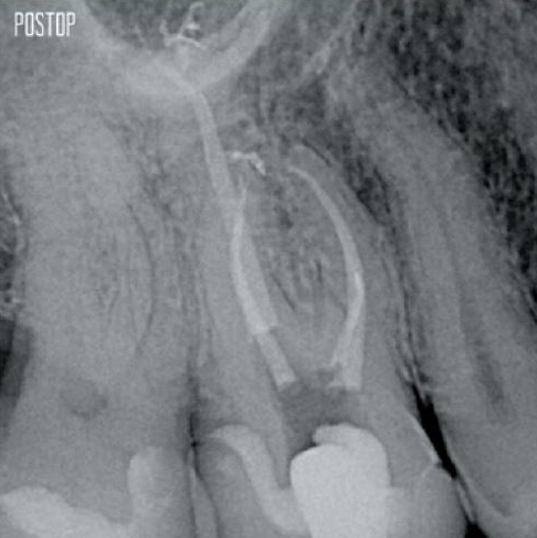

Photos courtesy of Dr. Ahmed Salman

Retaining dentin serves as the critical base for a quality restoration following root canal treatment. The more dentin preserved during an endodontic treatment, the more options there will be to perform a successful, durable restoration.1

Successful root canal treatment starts with adequate access to the pulp chamber. The ideal procedure provides access to root canal orifices with minimal loss of dentin.

A Conservative Endodontic Cavity (CEC) is the recommended with the TruNatomy® system.

The union of the file geometry, regressive tapers and the slim, highly-flexible wire enables efficient root canal treatment while removing only dentin where clinically needed.1

More dentin preserved. Appropiate shaping, irrigation, and obturation ensured.

Yes, the TruNatomy Conform Fit® gutta-percha points are designed to perfectly match the preparations made with TruNatomy files and ensure an optimal obturation.